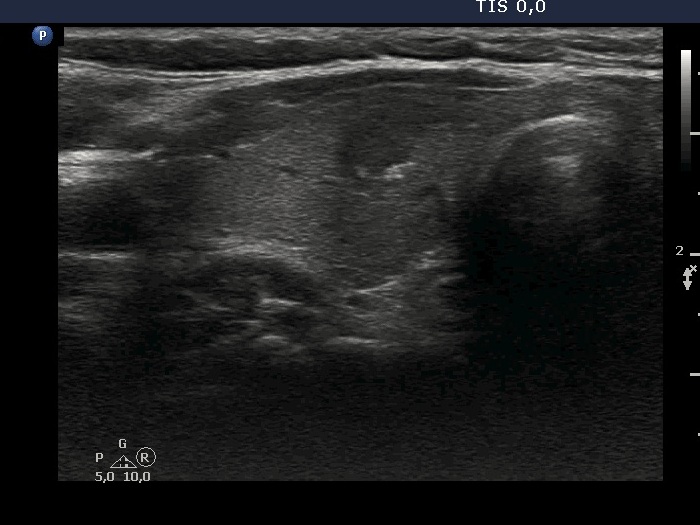

Ultrasonography. The thyroid was echonormal or minimally hypoechoic. There was a moderately hypoechoic nodule which had a cystic portion in the lower part. The nodule had lobulated margins and contained different hyperechoic figures. Beside figures caused either by posterior enhancement of proliferation of connective tissue, several ambiguous. bright granules were also found. Compared with the first measurement, the nodule is increased by more than 75% in volume.